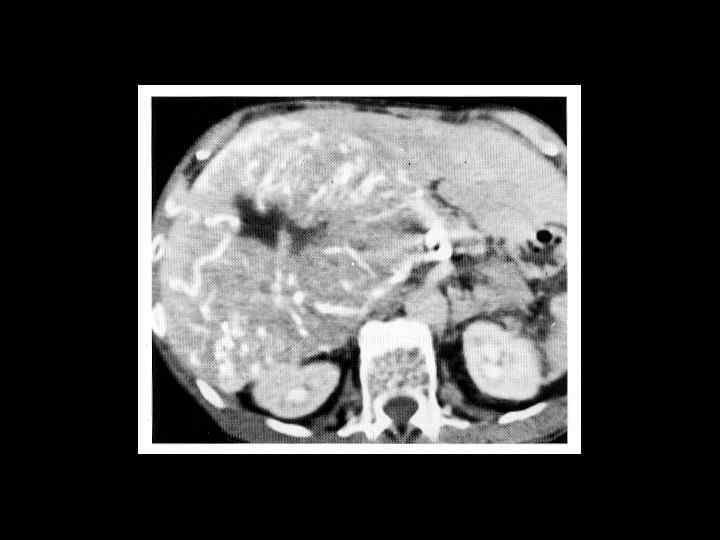

Тот же пациент